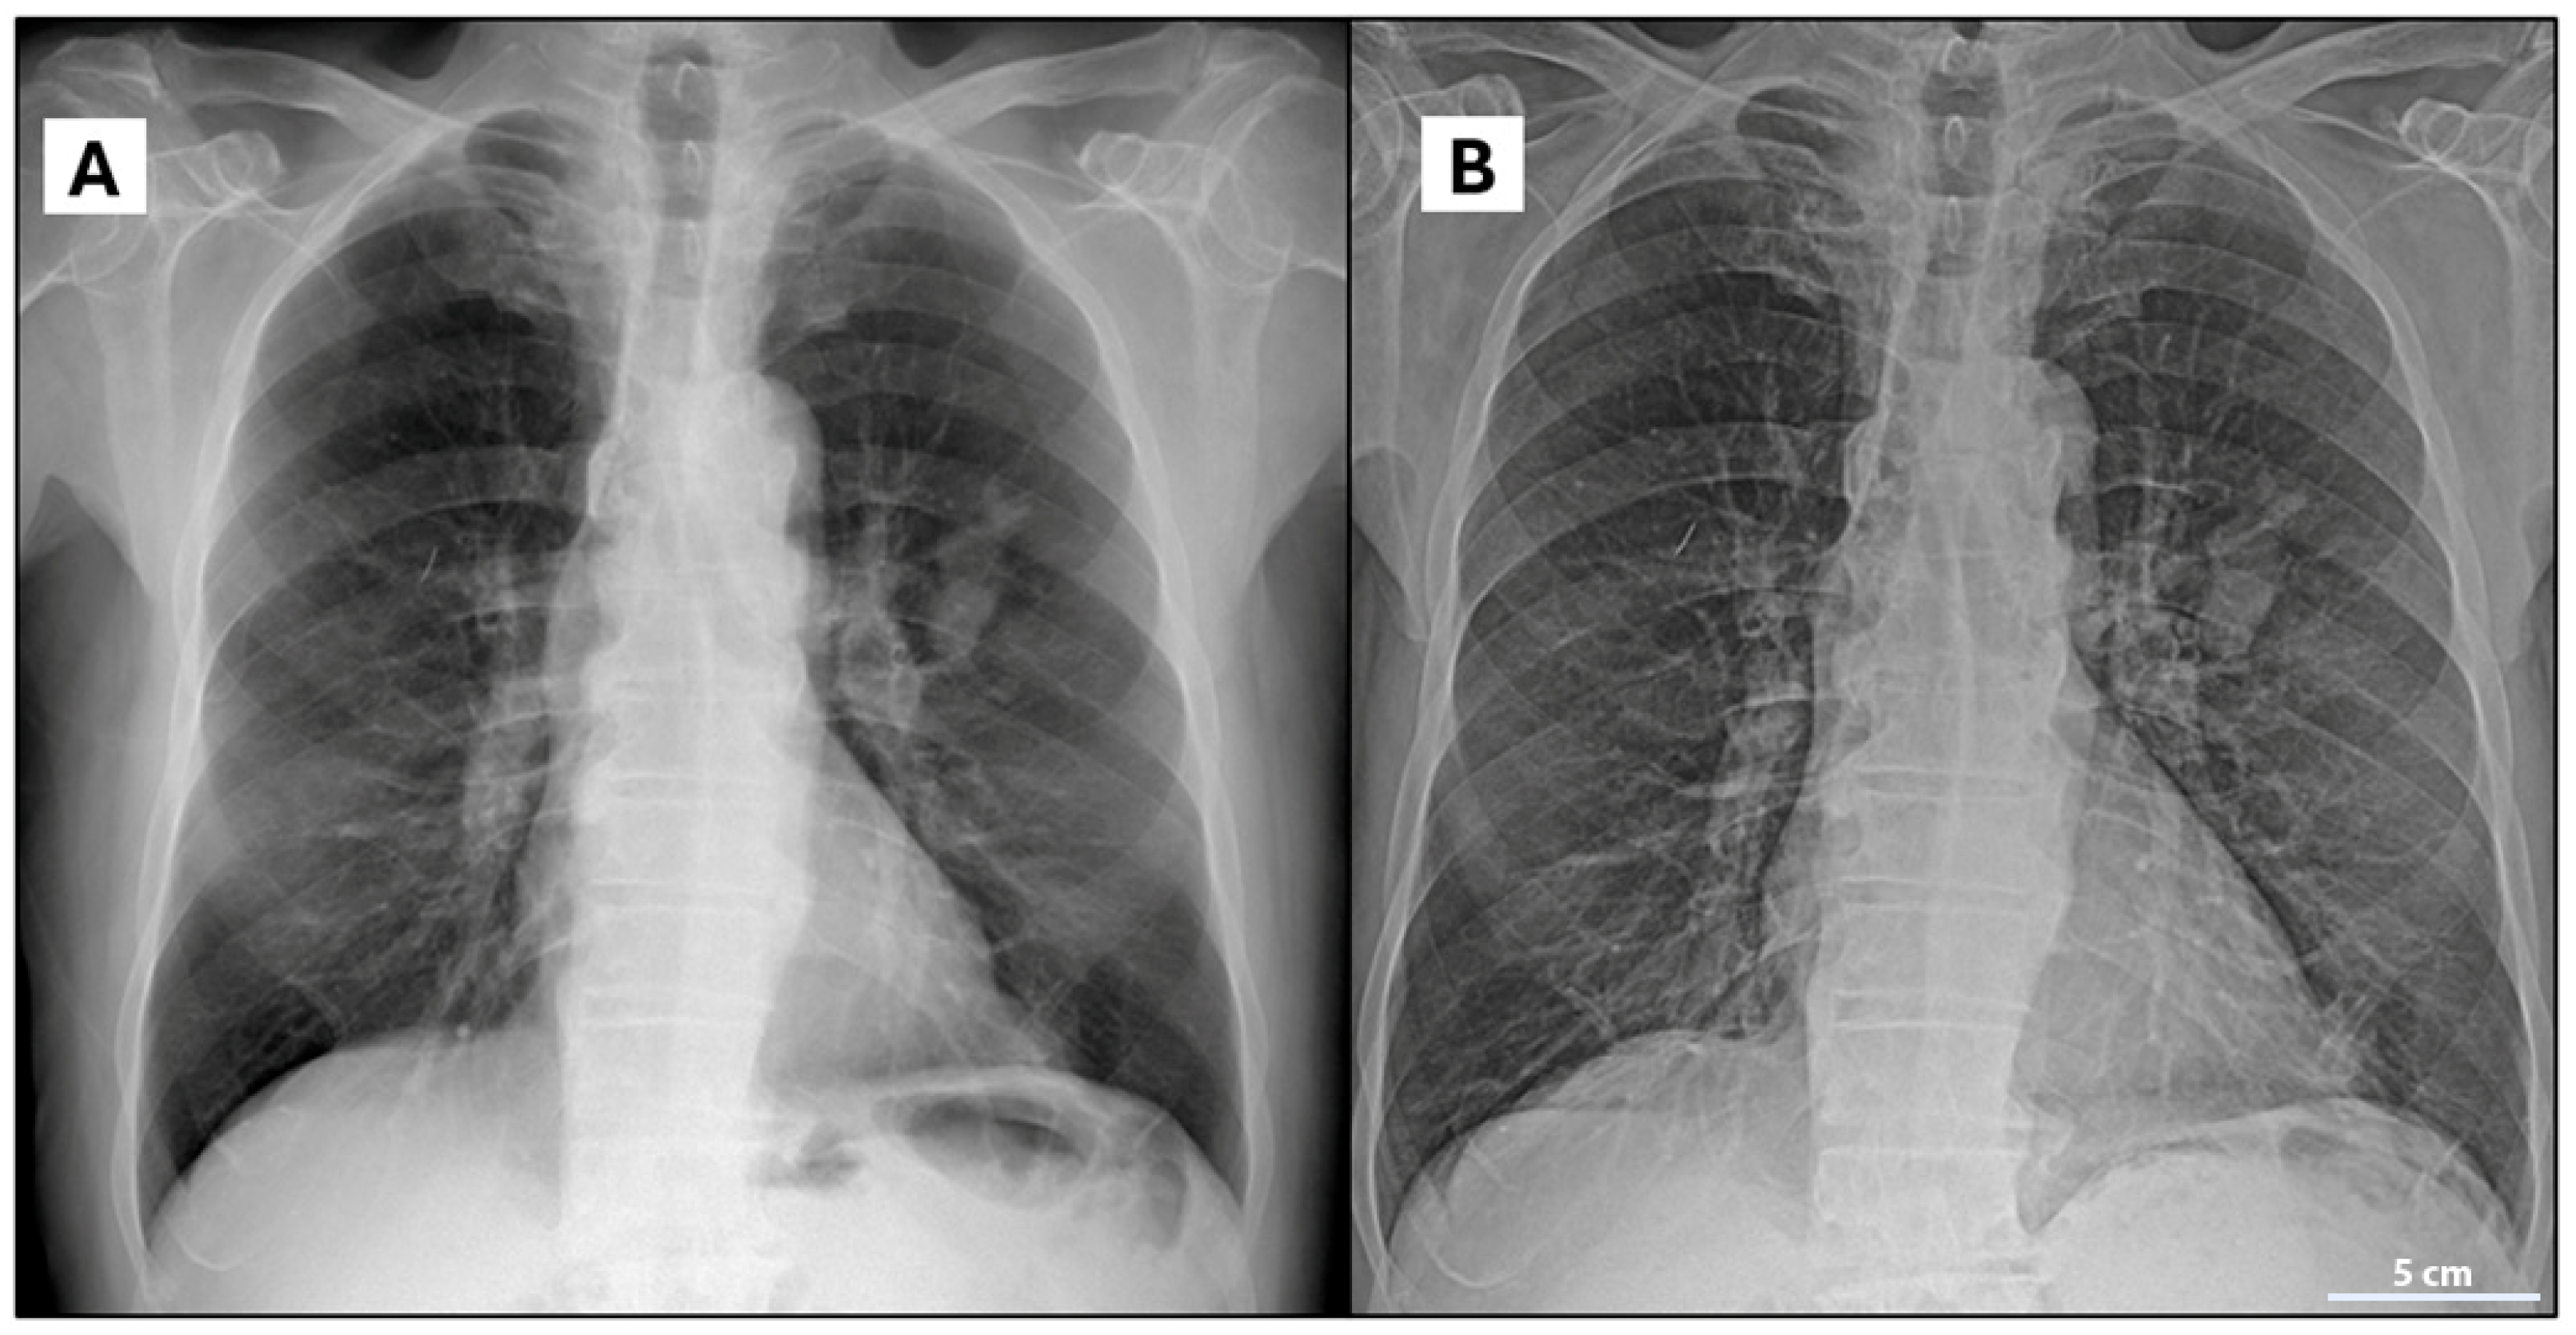

The A 76-year-old man, a former heavy smoker (80 pack-years), with a medical history of COPD, hypertensive heart disease, hyperuricemia, and benign prostatic hyperplasia, was admitted to the Pulmonology Unit at San Severo Hospital in January 2023 due hyperpyrexia, cough, and dyspnea. Blood tests revealed elevated inflammatory markers (ESR 58 mm/h, CRP 145 mg/L) and leukocytosis (white blood cells 14,500/mm3). Chest X-ray (Figure 1A) revealed a suspected consolidation in the lower left lung lobe, prompting treatment with meropenem, levofloxacin, and methylprednisolone. After clinical improvement, the patient was discharged with instructions to continue levofloxacin and prednisone at home.

Figure 1.

(A,B): Chest X-ray (A) performed before medical treatment; (B) follow-up chest X-ray after treatment, showing no significant changes in the pulmonary consolidation at the level of the left perihilar region.

A follow-up chest X-Ray (Figure 1B) performed 15 days later detected an oval-shaped mass with well-defined margins in the lower left lung lobe, raising suspicion of pulmonary neoplasm.